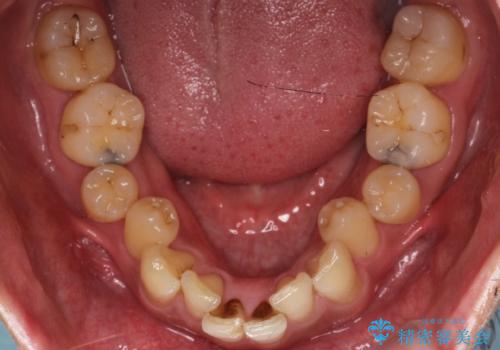

- 前歯のデコボコ(叢生)と、上下の歯の重なりが深い「ディープバイト(過蓋咬合)」を主訴にご来院されました。精密検査の結果、歯が並ぶスペースが不足しているため、上顎左右の小臼歯を抜歯することでスペースを確保し、全体の咬み合わせを改善する治療計画を立案しました。これにより、見た目の改善だけでなく、過度な咬み合わせによって生じる歯や顎への負担も軽減することを目指します。

今回の矯正治療では、まず歯が並ぶスペースを確保するため、上顎の小臼歯を抜歯しました。抜歯によってできたスペースを利用して前歯を奥へ移動させ、デコボコを解消。同時に、奥歯の咬み合わせを調整することで、深すぎた咬み合わせであるディープバイトも改善しました。治療の結果、長年気にされていた前歯のデコボコが解消され、理想的な歯並びに。さらに、正しい咬み合わせを獲得したことで、機能的にも安定した美しい口元になりました。